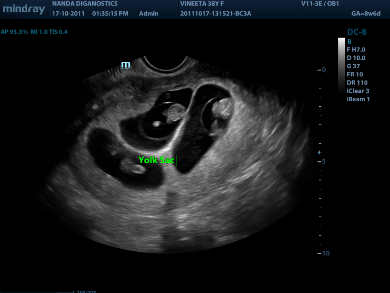

Ηχοβόλος κεφαλή τύπου Convex Array SC5-1N, τεχνολογίας μονού κρυστάλλου από 1,2 MHz έως 6,0 MHz με δυνατότητα επιλογής διαφορετικών συχνοτήτων στο B-Mode, Doppler, Έγχρωμο Doppler για απεικόνιση άνω κάτω κοιλίας, ουρολογίας, αγγείων, αορτή, γυναικολογίας μαιευτική κλπ.